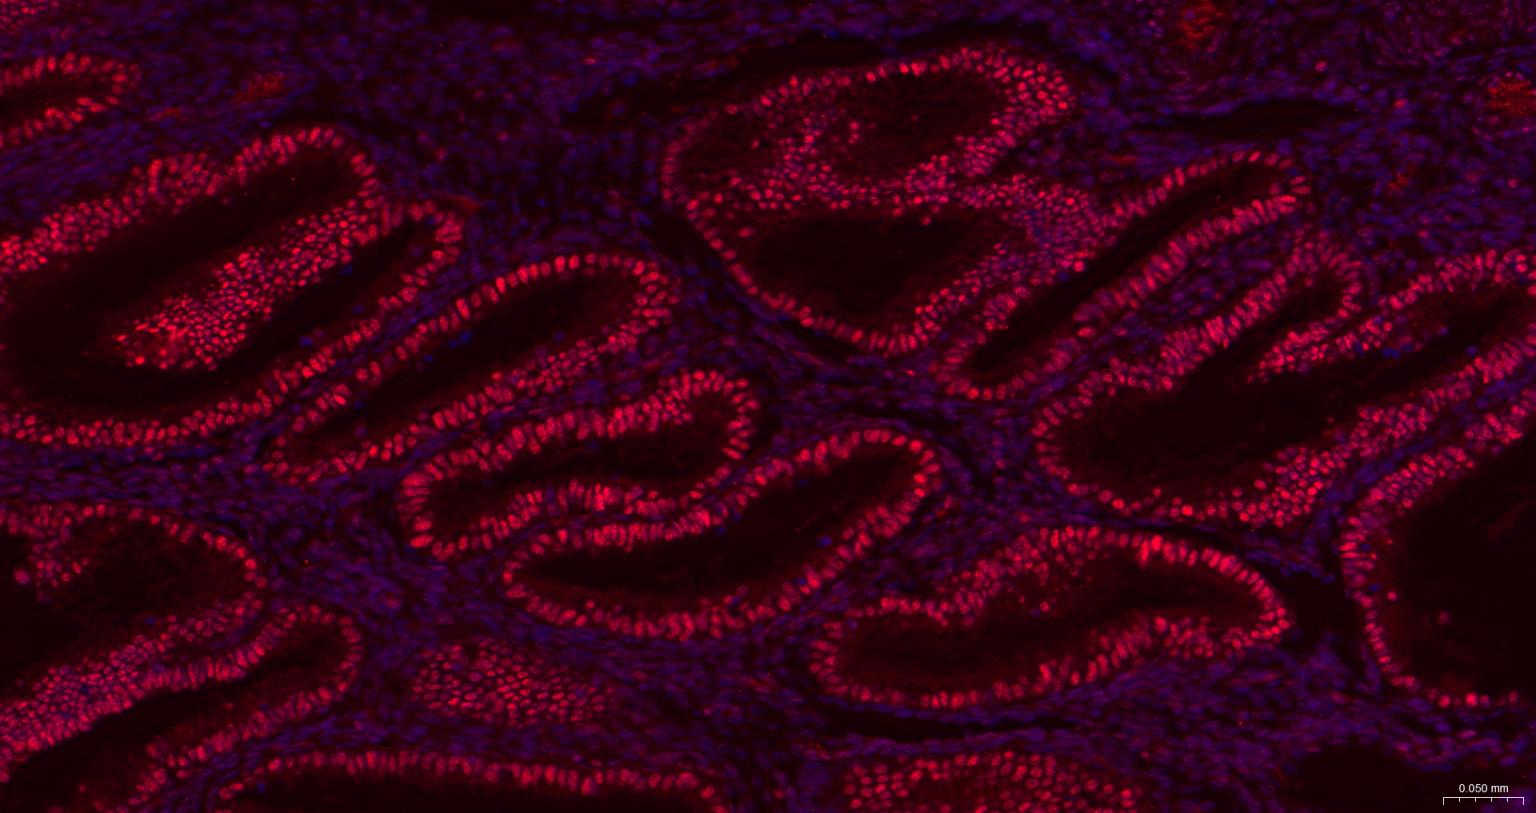

Paraformaldehyde-fixed, paraffin embedded Rat Colon; Antigen retrieval by boiling in sodium citrate buffer (pH6.0) for 15 min; The section was incubated with Oct-1 Monoclonal Antibody, Unconjugated (bsm-63240R) at 1:200 overnight at 4°C, followed by conjugation to the bs-0295G-HRP and DAB (C-0010) staining.

Paraformaldehyde-fixed, paraffin embedded Mouse Colon; Antigen retrieval by boiling in sodium citrate buffer (pH6.0) for 15 min; The section was incubated with Oct-1 Monoclonal Antibody, Unconjugated (bsm-63240R) at 1:200 overnight at 4°C, followed by conjugation to the bs-0295G-HRP and DAB (C-0010) staining.